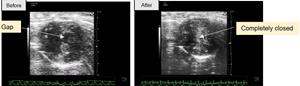

The following are still images taken of the echocardiograms (i.e. ultrasound to create images of the heart) of the bat’s heart. They show the two-dimensional (2D) short-axis view of the left ventricle (LV) chamber, before and after dobutamine administration. Both images show a moment during a contraction of the bat’s heart.

(L-R): Echocardiograms of the bat’s heart, showing before and after dobutamine administration respectively.

On the left image, there is a small gap in the middle of the LV chamber during a contraction of the heart. On the right, the LV chamber is completely closed during contraction, suggesting a more powerful pump of blood.